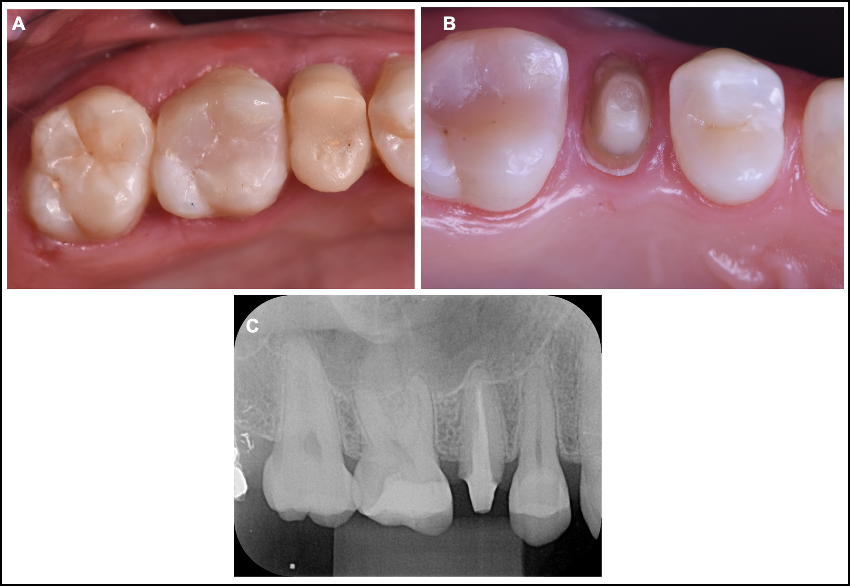

Figura 1. Vista oclusal e vestibular do segundo pré-molar direito com restauração provisória com resina acrílica; B. preparo coronário insatisfatório, com quantidade de desgaste insuficiente na superfície oclusal, direção de inserção da coroa alterada e término cervical irregular; C. Rx mostrando pino de fibra de vidro e tratamento endodôntico satisfatório.